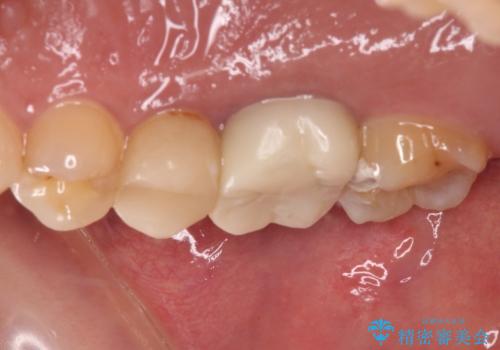

不快感の強い奥歯 オールセラミッククラウンでのむし歯治療

- とにかく奥歯に不快感を感じるとのことで来院された患者様です。

神経近くにまで及んでいる大きなむし歯や、歯肉の中深く、骨の近くにまでむし歯が進行している歯など、問題の多い状態でした。

神経を温存するための処置や、歯肉深くにまで及んだむし歯を改善するための歯周外科処置などを行っていき、オールセラミッククラウンにて補綴治療を行うこととしました。

術前の診断では神経が温存できるか否か、際どい状況でしたが、治療開始前の海外への帰省の際に自発痛(何もしなくてもズキズキ痛む)の症状が出てしまい、根管治療が必要となってしまいました。